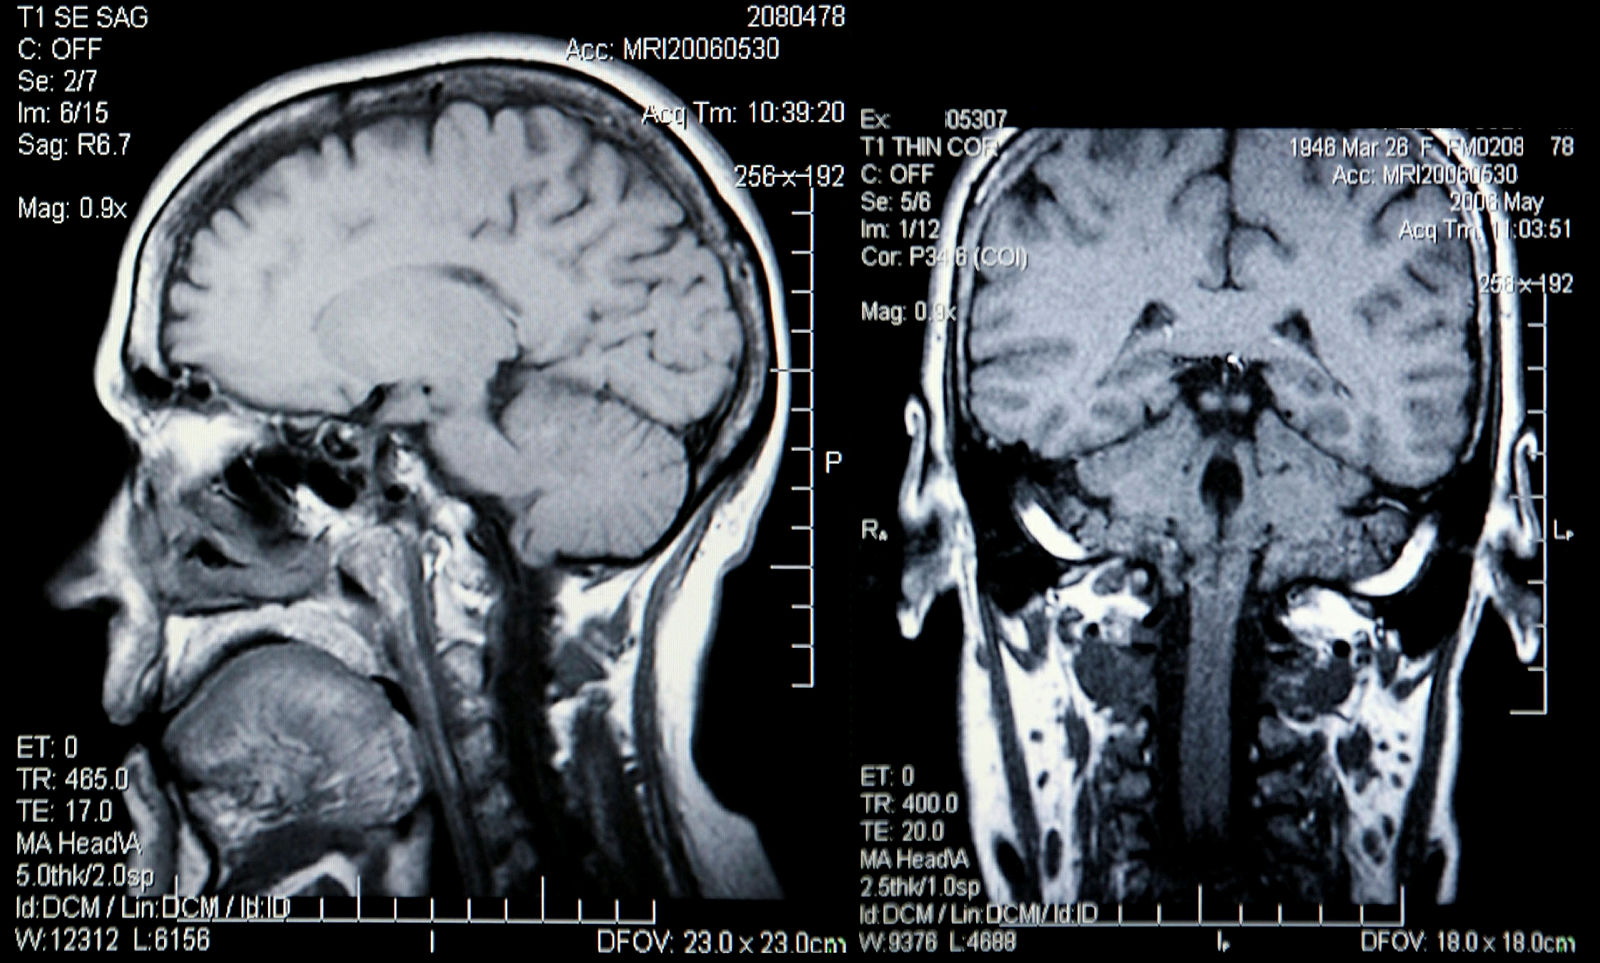

Røntgenapparat på loftstuen

<<Det fremgår klart av Fylkesmannens uanmeldte tilsyn i bolig, at forholdene var uegnet for å yte helsetjenester. Vi viser til at røntgenapparatet var installert i loftstuen, at journalopplysninger lå usikret, at det lå brukt nål og tupfer med jod/desinfeksjonsvæske på instrumentbordet ved pasientbenken og at legemidler som lå fremme ulike steder i flere tilfeller var utgått på dato (kontrastvæske, bedøvelse, kvalmestillende, antibiotika mv.)>>, skriver Helsetilsynet.

Statens strålevern sin tilsynsrapport peker på at røntgenapparat/C-bue skal betjenes av radiograf eller lege med relevant spesialistgodkjenning, eventuelt tannlege med spesialistgodkjenning i kjeve og ansiktsradiologi.

Verken nevrokirurg eller tidligere lege har dokumentert medisinsk kompetanse som påkrevd i strålevernforskriften for å betjene et slik røntgenapparat.

<<Din norske autorisasjon som lege innebærer heller ikke spesialistgodkjenning til å bedrive radiologisk diagnostikk>>, står det i Helsetilsynets avgjørelse.